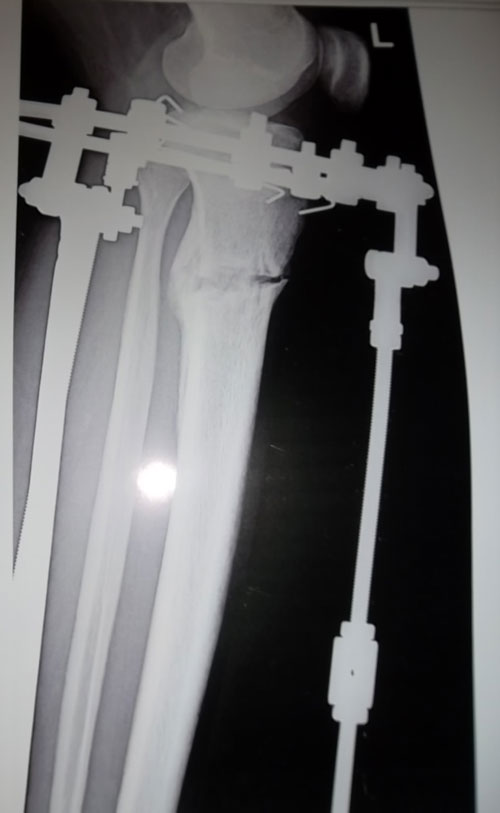

Сообщение Sekretar Onipko »

7-ой день после операции, начало круток.

SAM_4032.JPG